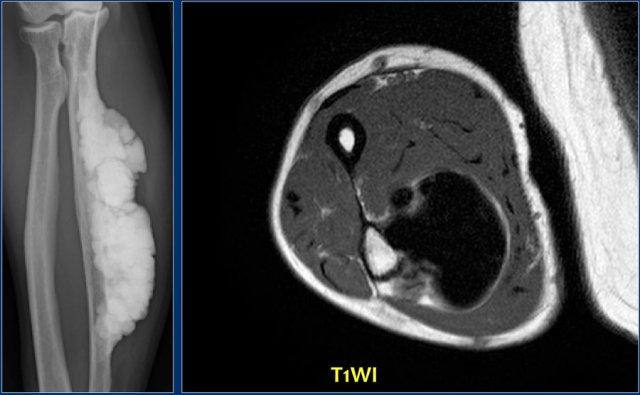

Đây là hình ảnh Melorheostosis của xương trụ với hình ảnh giống như sáp nến.

U xương bề mặt (surface osteosarcoma) có thể được xem xét trong chẩn đoán phân biệt

Hình ảnh MR T1 trục cho thấy tín hiệu thấp đồng nhất do sự lắng đọng xương đặc.